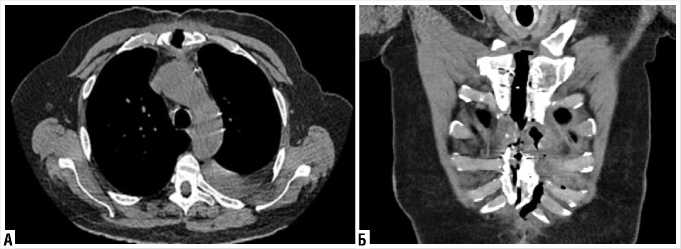

На КТ-ОГК отмечался диастаз краев грудины до 12 мм, края грудины местами нечеткие с признаками узурации, между краев грудины скопление воздуха (Рис. 2).

Рис. 2. КТ-грудины, средостения и плевральных полостей. Несостоятельность проволочного первичного остеосинтеза, признаки тотального остеомиелита тела и рукоятки грудины.